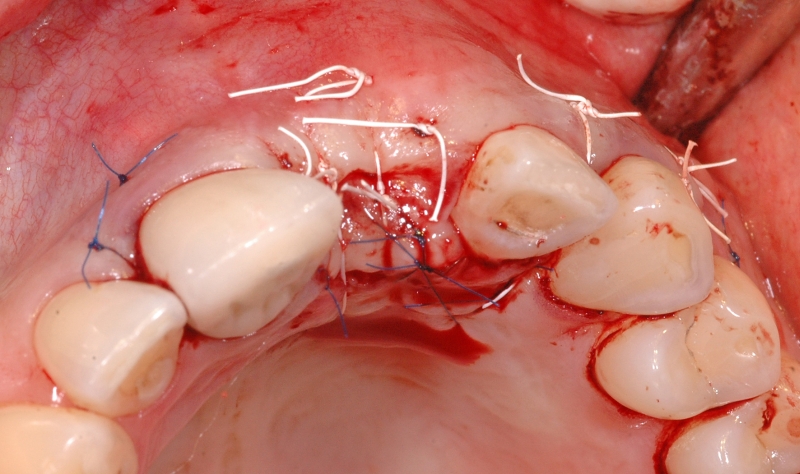

10/18 - Fixation of mucoderm® and suturing of the flapGBR together with soft tissue augmentation with mucoderm® and maxresorb® - Dr. S. Scherg